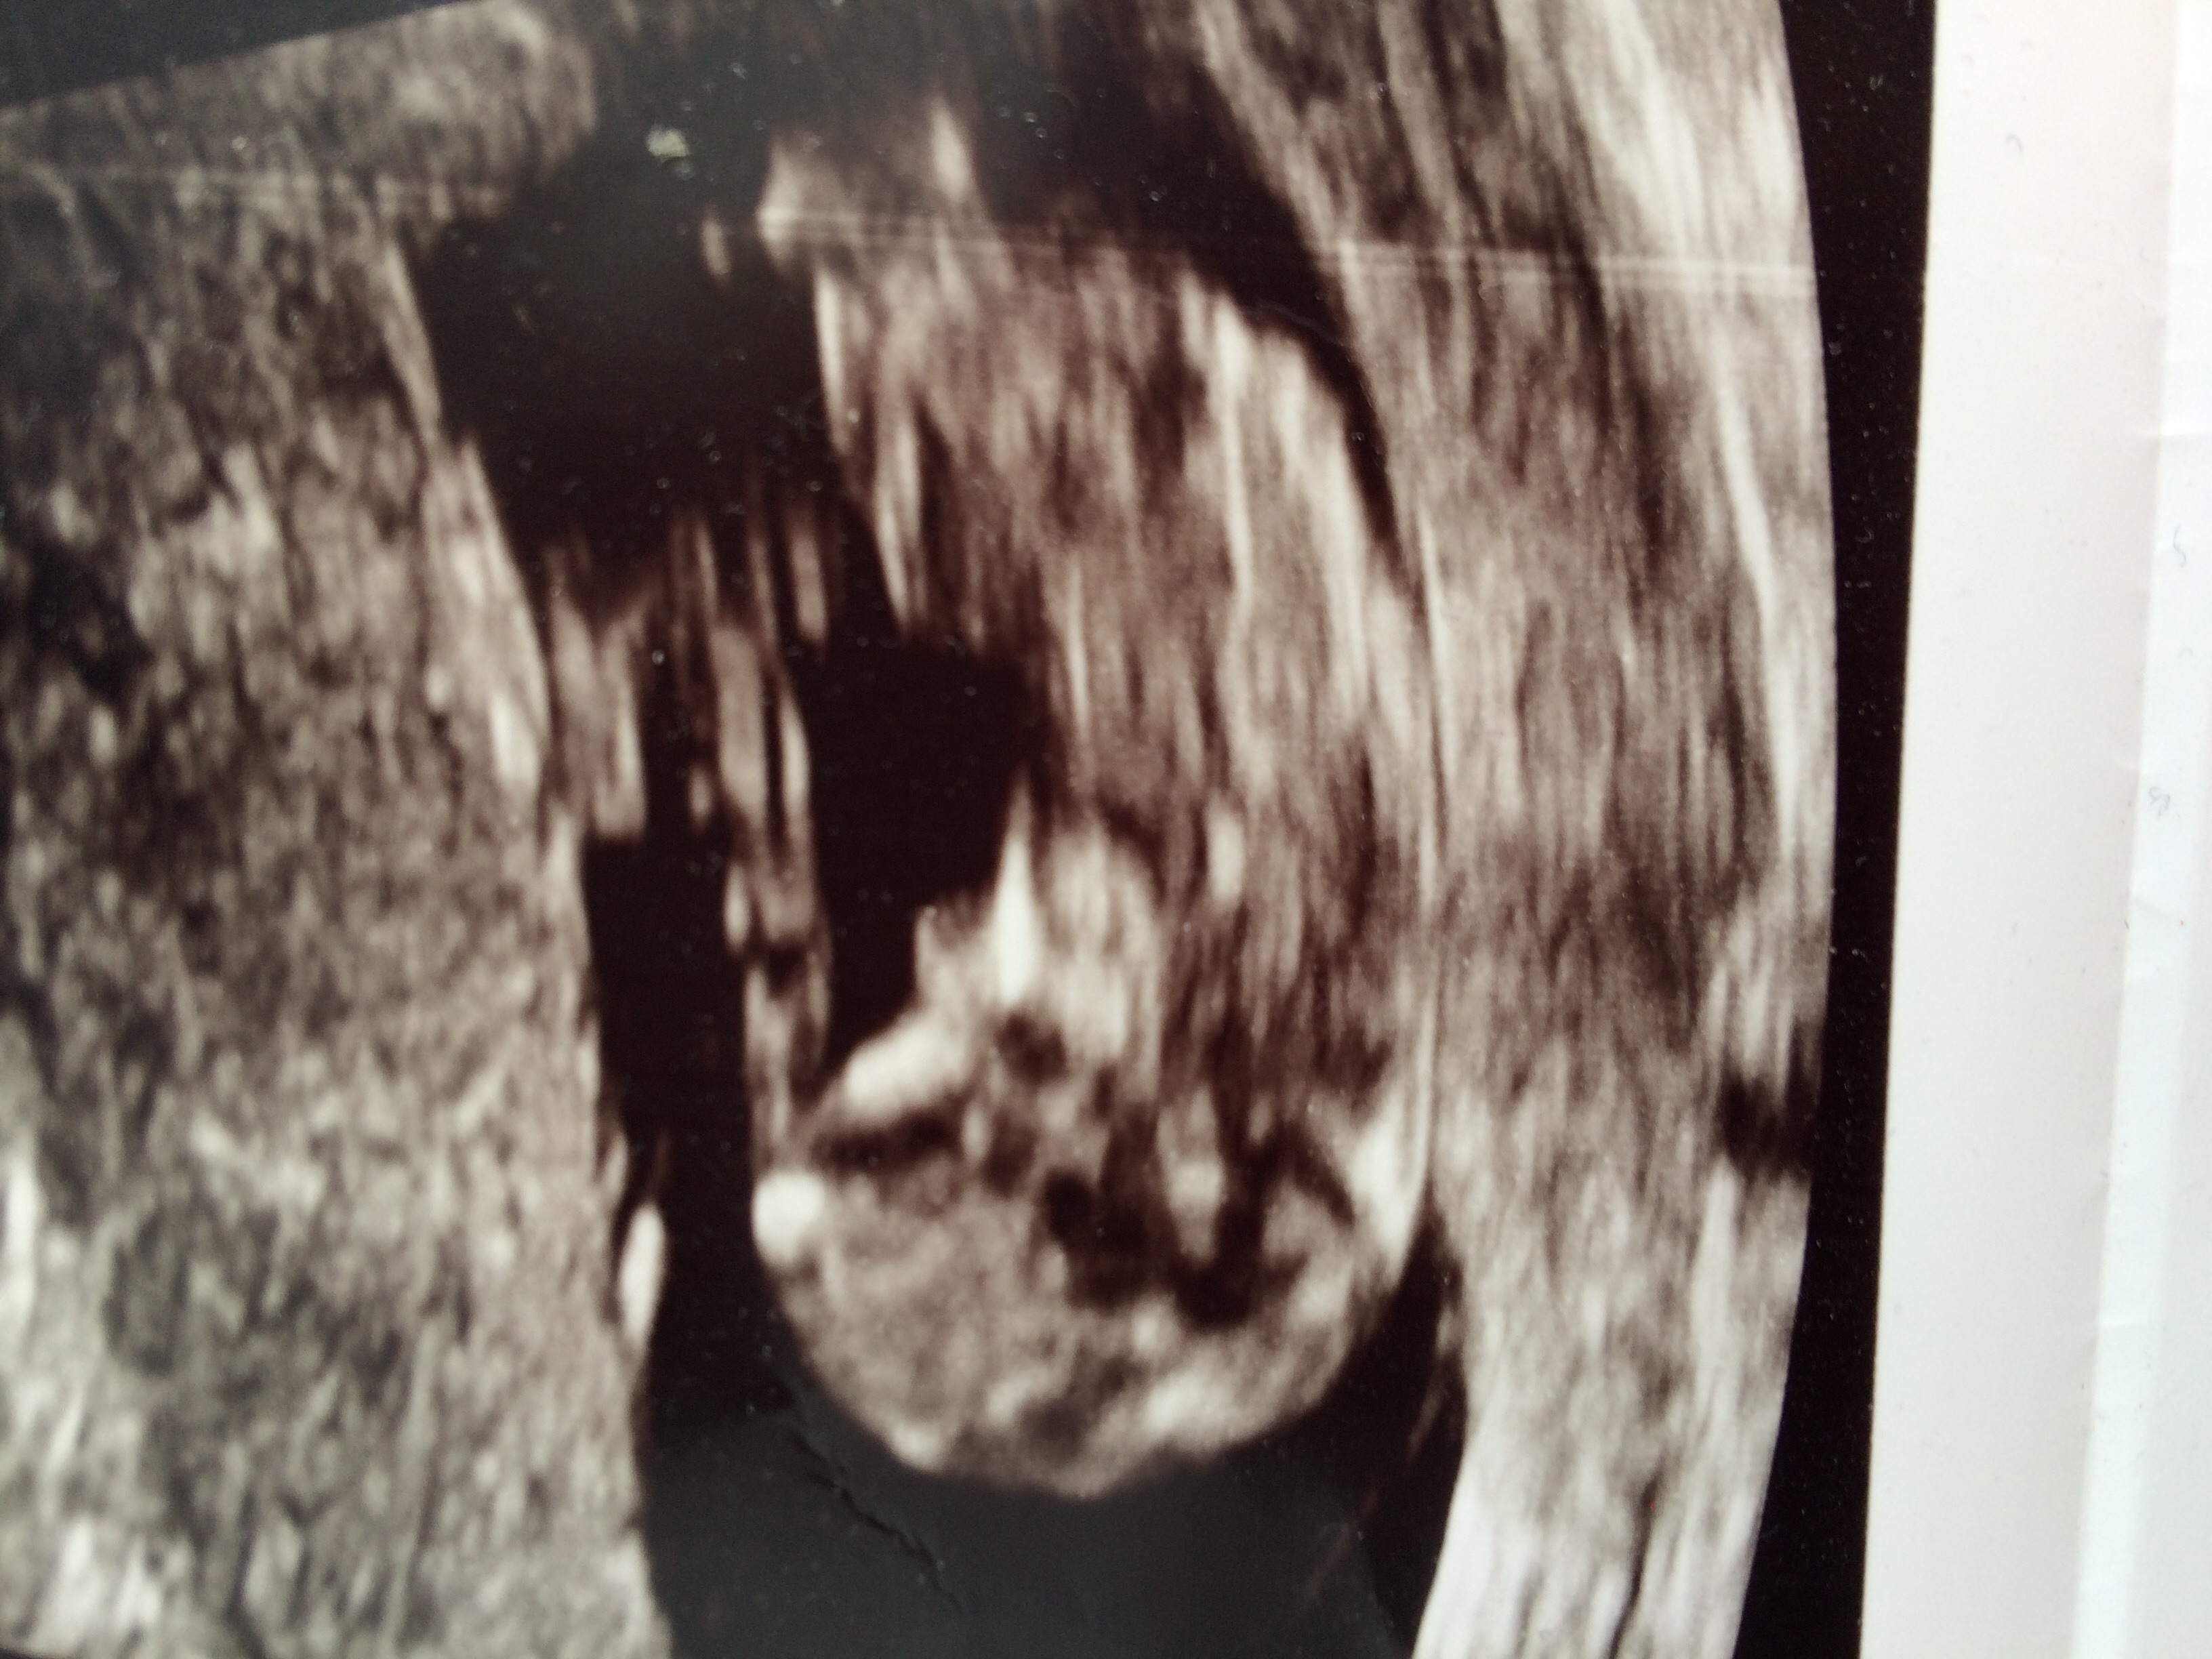

Gender scan tomorrow, any last minute guesses? I was 11+3 here.

If that's a nub I see on the second picture, thinking boy but it's still too early to say for certain.

I thought I could see a girly nub on the second picture. Enjoy your scan :)